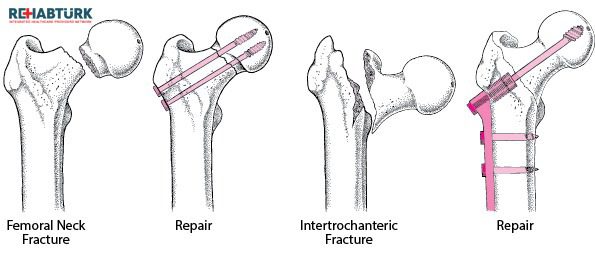

ما نوع الجراحة كسر الورك التي أحتاجها؟

سيحكم طبيبك على صحتك والطريقة التي كسرت بها وركك ليقرر أي من الطرق التالية هو الأفضل:

- الإصلاح الداخلي . يقوم الجراح بإدخال مسامير في عظامك. هذا يبقيها متماسكة بينما يشفى الكسر. في بعض الأحيان يقومون بتوصيل المسامير بلوحة معدنية موضوعة على طول عظم الفخذ.

- الاستبدال الجزئي لمفصل الورك . يتم ذلك عادة في حالة تلف أطراف العظم المكسور أو في غير مكانه. سيقوم الجراح باستبدال الجزء العلوي من العظم بطرف اصطناعي معدني. هذا بديل عن جزء مفقود.

- استبدال مفصل الورك . يعد هذا خيارًا جيدًا إذا كان مفصلك قد تضرر بسبب التهاب المفاصل أو إصابة أخرى. يستبدل الجراح عظم الفخذ العلوي (عظم الفخذ) والمحجر الموجود في عظم الحوض بأطراف اصطناعية.

تعد خيارات استبدال مفصل الورك اختيارات جيدة إذا كان الكسر يضر بإمداد الدم للجزء الكروي من مفصل الورك. لذلك هذا هو الجزء الذي يسمح لأعلى رجلك بالانحناء والدوران. عدم وجود ما يكفي من إمدادات الدم يمنع العظام من الشفاء أيضًا.